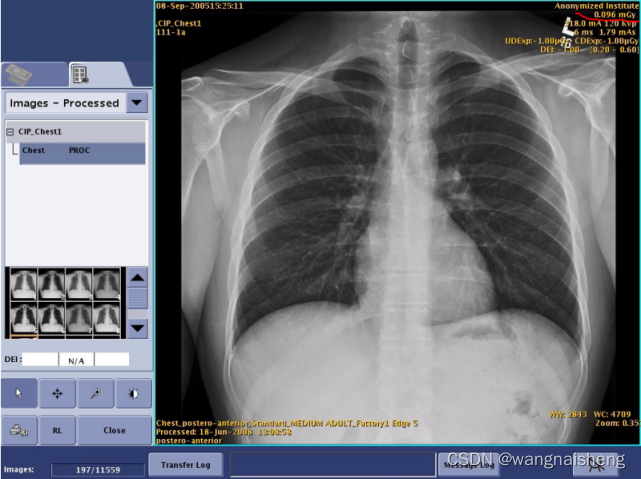

图中所示,DR的曝光参数:kV为120kV,mA为320mA,mAs为0.46,那么在这一次曝光中,曝光的功率为3.84kW,曝光时间为1.4ms,一次曝光产生的总热量为55.2HU。

下图是GE一款DR曝光后采集的图像,右上角为曝光参数,有曝光条件和产生的辐射剂量。